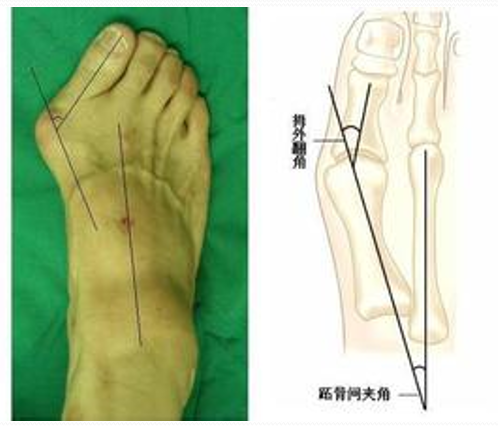

1:前后位观察和测量拇外翻角(HAA)  :拇趾跖骨中轴线与近节趾骨中轴线之夹角。正常为15°~20°

第1、2跖骨间夹角(IMA):  第1、2跖骨中轴线之夹角。正常为9 °拇外翻时此角通常大于正常。

X线表现与测量

足的x线测量对于进一步了解拇外翻的病理及设计手术方案是非常重要。负重足的基本功能,很多足的畸形在负重状态下可以表现得更清楚。一些测量指标在负重和非负重状态下可以明显不同。足部各种x线测量一般都是在足负重位摄片下完成。手术前常规需要拍摄患足负重位、前后位和侧位,根据需要拍摄足的非负重位内旋斜位和籽骨轴位。